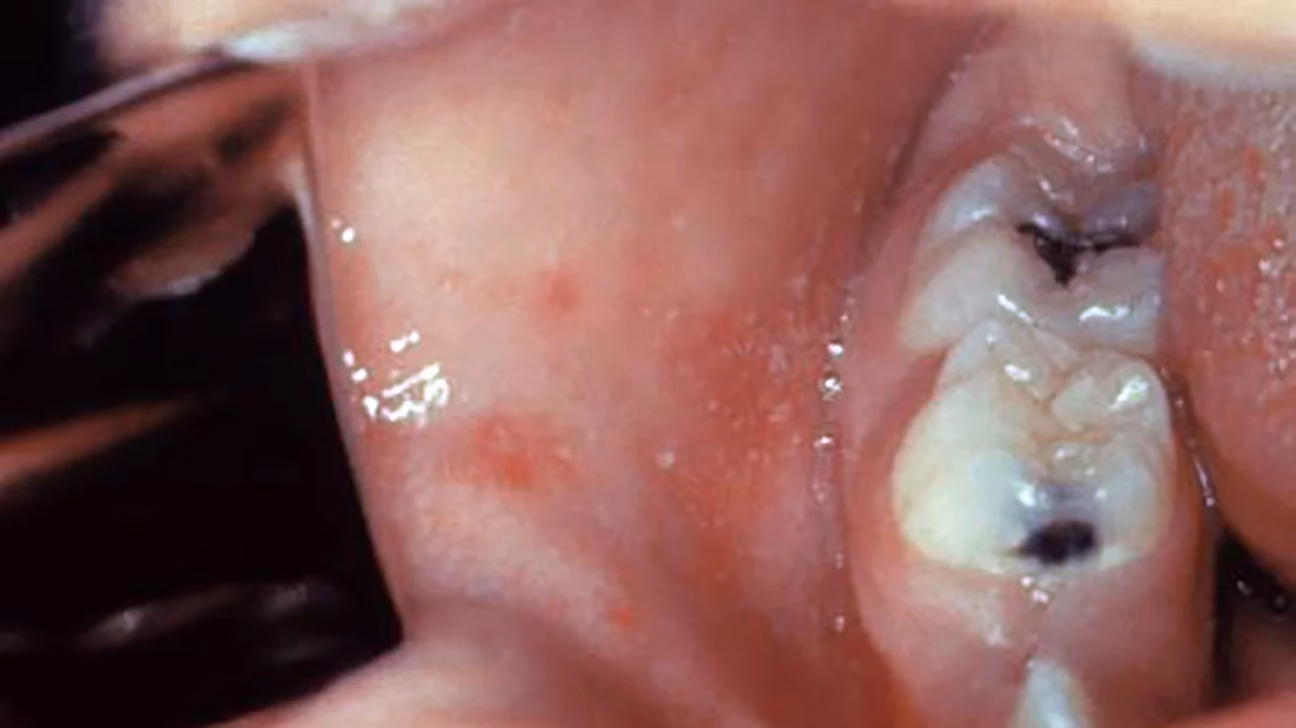

- Den indledende fase (Prodromalstadiet): Denne fase varer normalt 4-7 dage og minder i starten om en kraftig forkølelse. Symptomerne inkluderer høj feber (ofte over 40°C), en tør, gøende hoste, løbende næse og røde, vandede øjne, der er følsomme over for lys. Et af de mest karakteristiske tegn i denne fase er fremkomsten af små, hvide pletter på indersiden af kinderne, kendt som Kopliks pletter. Disse er et stærkt tegn på mæslinger.